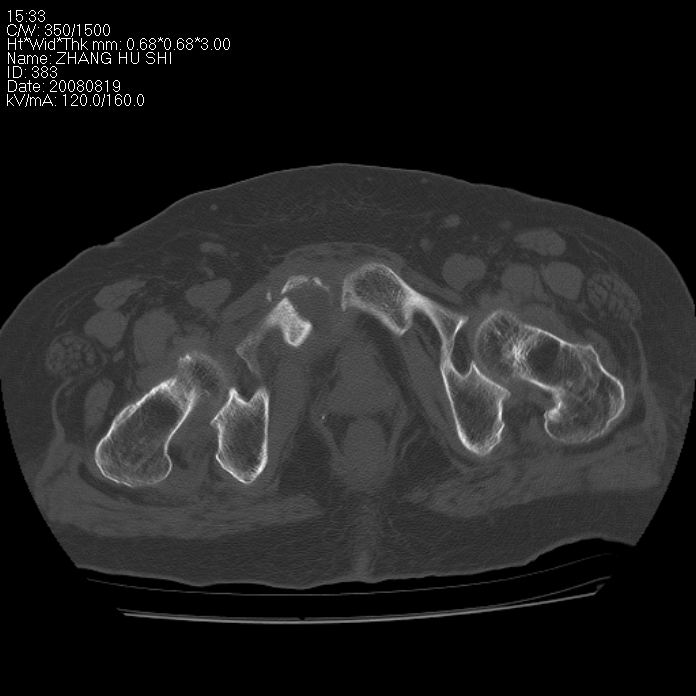

标题: CT15287:女 93岁 右髋关节疼痛 原左侧粗隆间骨折 CT发现右耻 [打印本页]

标题: CT15287:女 93岁 右髋关节疼痛 原左侧粗隆间骨折 CT发现右耻

支持转移并周围软组织侵犯右闭孔内肌侵犯,但tb不能完全除外。

耻骨软骨肉瘤可能性大